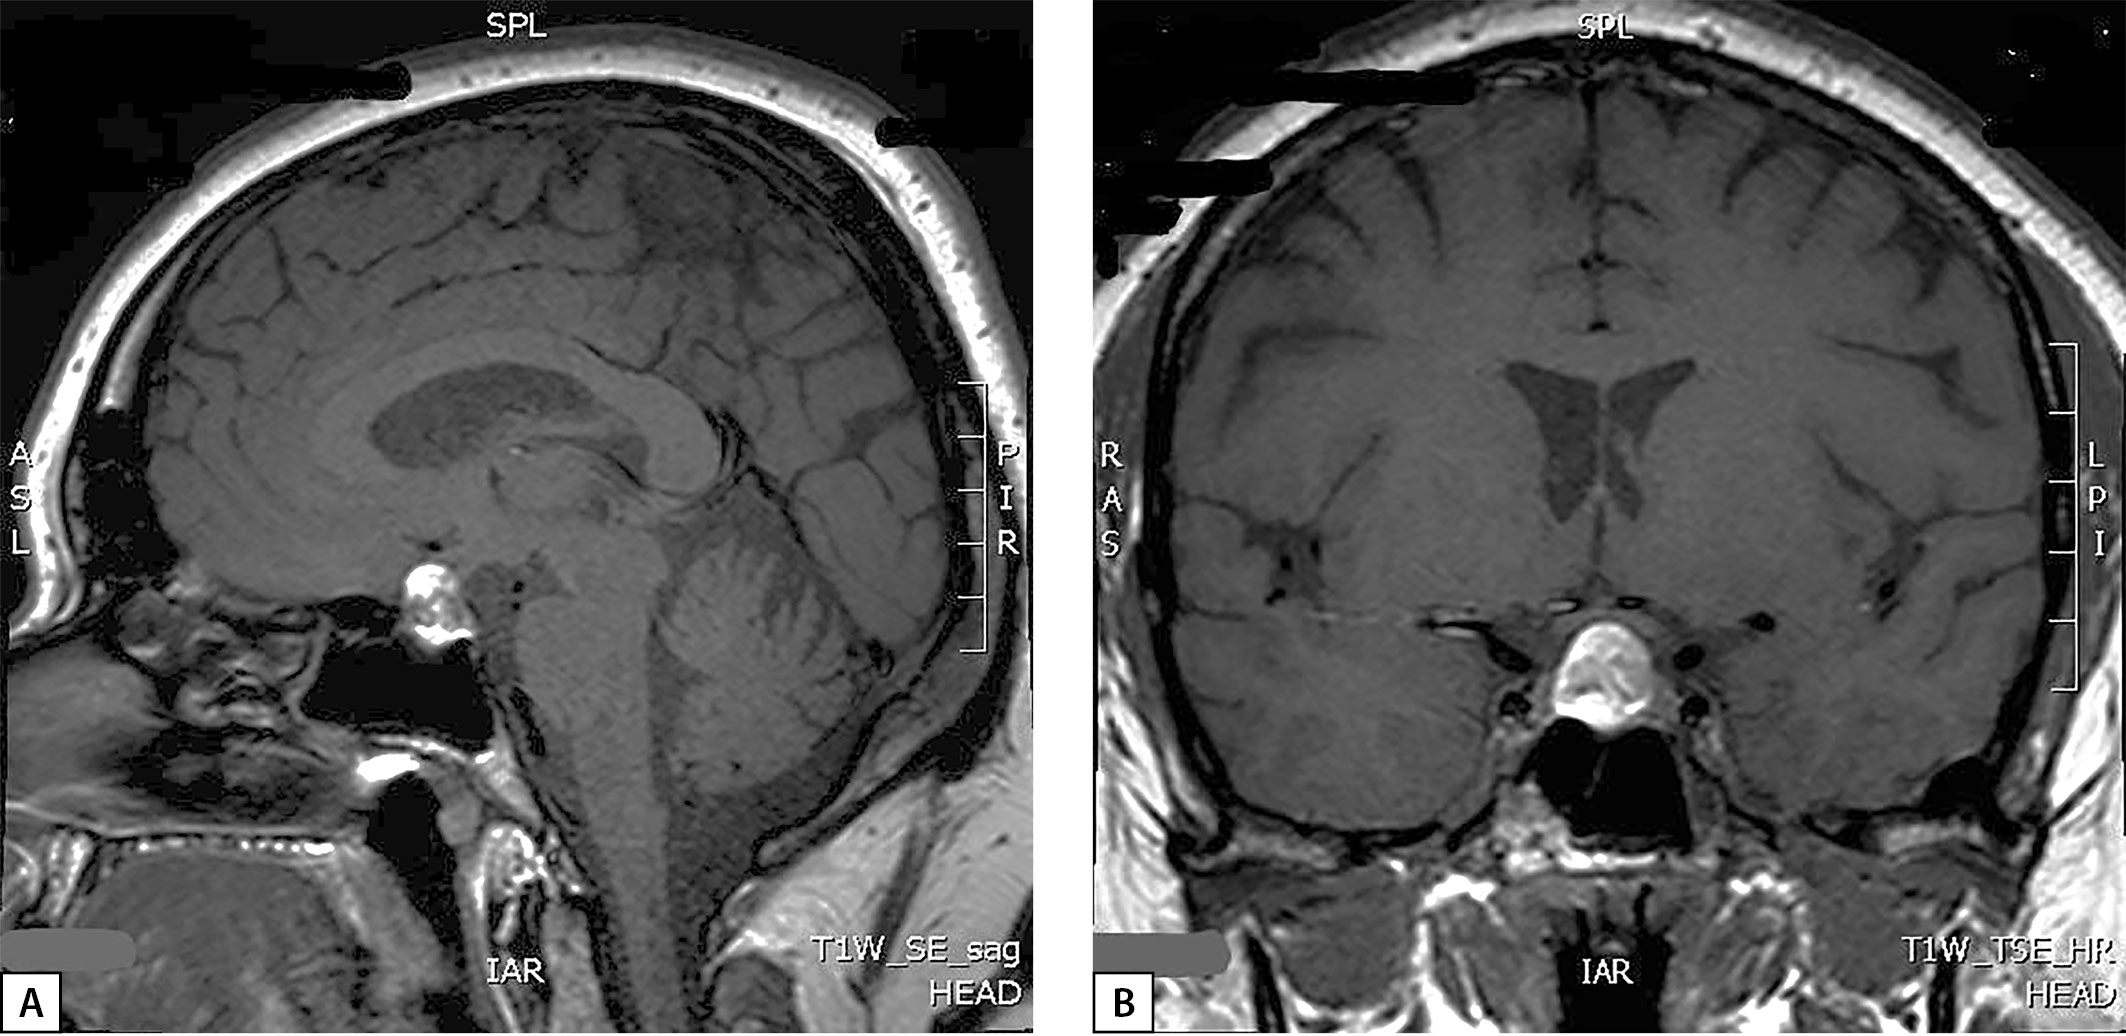

На следующем этапе диагностического поиска проводится уточнение причин гиперкортицизма, наиболее частой причиной которого является АКТГ-продуцирующая опухоль гипофиза (кортикотропинома), однако могут быть случаи и кортизол-продуцирующих опухолей надпочечников или эктопической продукции АКТГ нейроэндокринными опухолями внегипофизарной локализации. Исследован суточный ритм АКТГ (физиологический ритм отсутствовал) и проведена большая дексаметазоновая проба (табл. 1), которые подтвердили наличие АКТГ-­зависимого гиперкортицизма. По данным МРТ гипоталамо-гипофизарной области (на аппарате со сверхвысоким напряжением магнитного поля 3,0 Ел) без контрастирования: в проекции увеличенного в размерах турецкого седла и супраселлярной цистерны срединно выявлено объемное образование округлой формы с четкими ровными контурами, размерами 17×15×12 мм, неоднородной структуры: преимущественно гиперинтенсивное на Т1-ВИ (взвешенных изображениях) и Т2-ВИ с участками гипоинтенсивного сигнала (рис. 1). Для исключения участков кровоизлияний была проведена КТ головного мозга с контрастированием: в полости турецкого седла определяется округлое объемное образование с супраселлярным распространением, с четкими ровными контурами, размерами 17×12×15 мм; структура образования неоднородная; в нижних отделах плотность образования при нативном сканировании — 53 ед. Н, в верхних — 39 ед. Н; после внутривенного контрастного усиления отмечалось накопление контрастного препарата только нижними отделами образования; КТ-данных за кровоизлияние в опухоль не получено.

Рисунок 1. Снимки МРТ гипофиза в сагиттальной (А)

и фронтальной (В) проекциях пациентки М., 33 года.

Визуализируется супра-эндоселлярная аденома гипофиза.